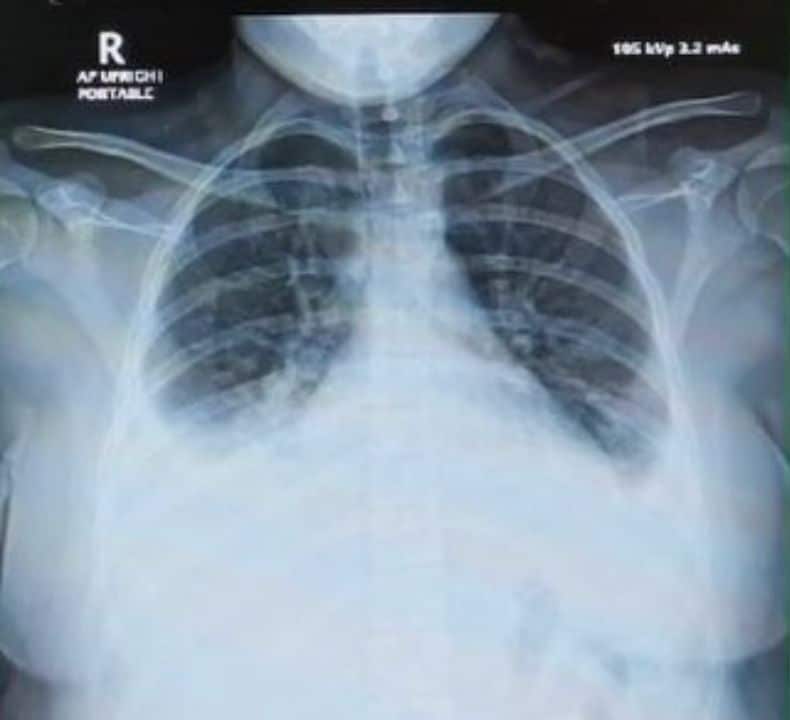

The patient developed severe lung inflammation and needed high-flow oxygen, along with antibiotics and steroids. The doctor said the tourist later recovered, and follow-up tests showed a normal chest X-ray.